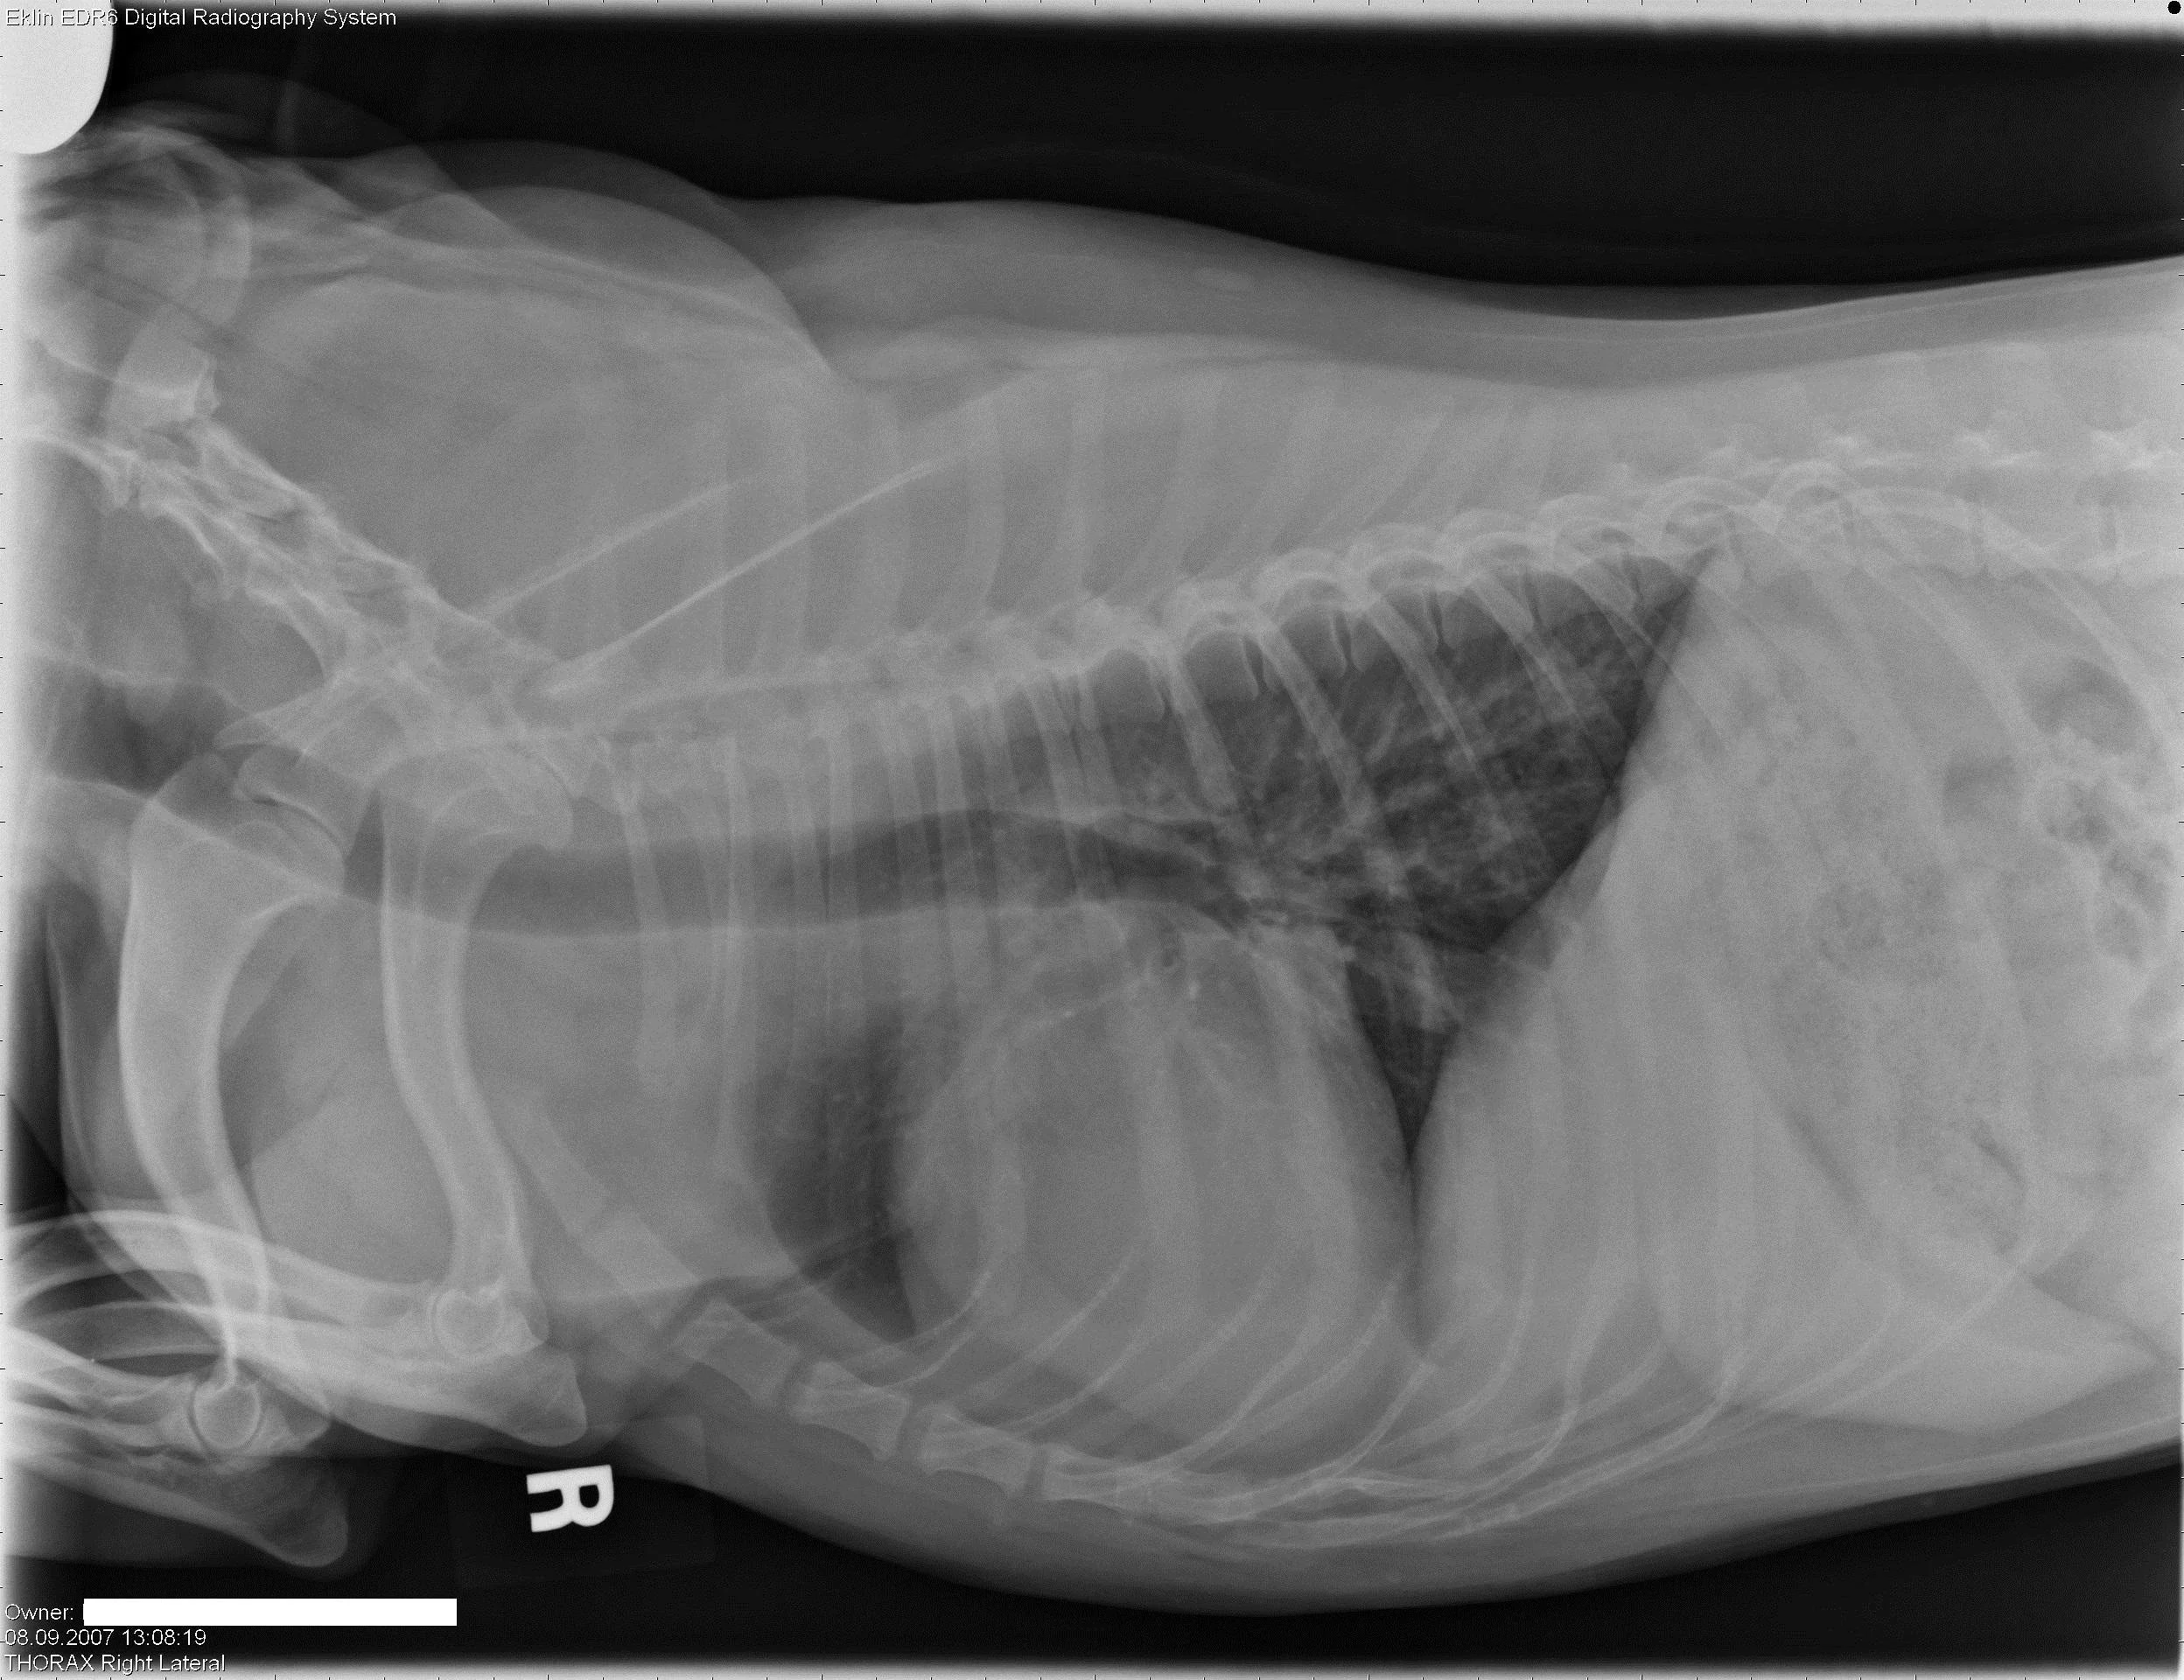

All in Reproductive